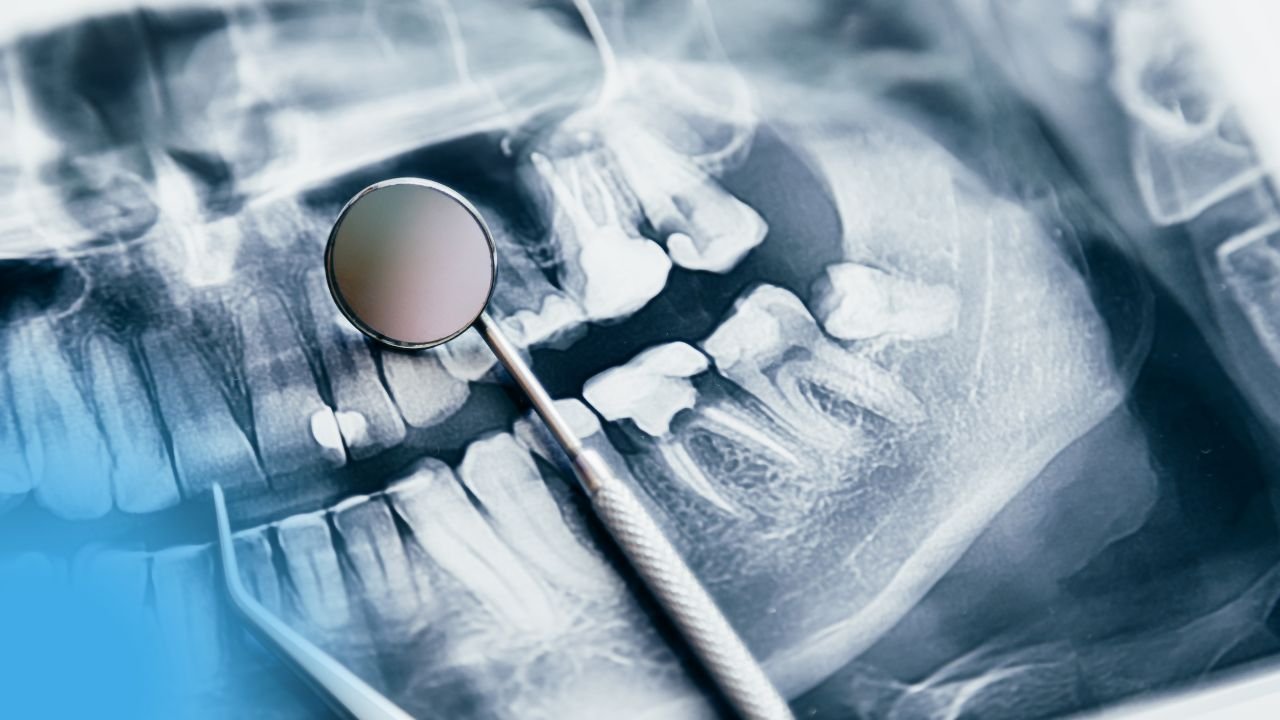

Explorations radiologiques en odontologie pédiatrique / Pédodontie

Explorations radiologiques en odontologie pédiatrique / Pédodontie Évaluation du besoin d’un examen radiologique Objectifs de l’examen radiographique L’examen radiographique a...